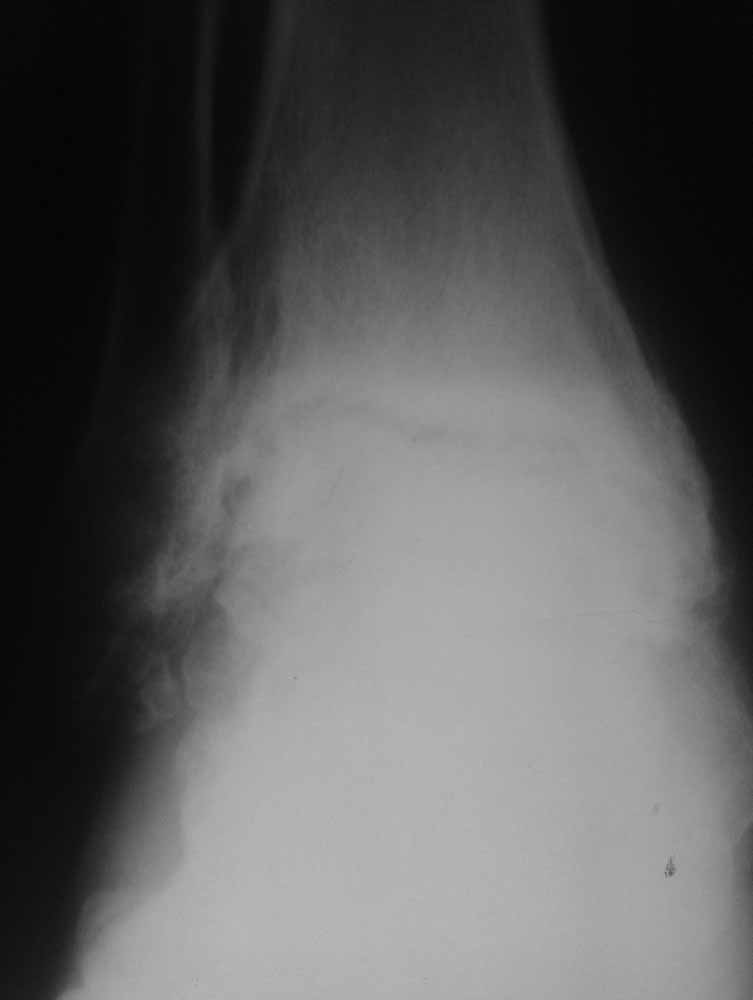

Опять прошу прощения за качество фото, но принципиальные моменты мне кажется, что видны.

Из того, что я вместе с лучевыми диагностами разглядел - нельзя исключить остеомиелит (?) - есть краевая реакция, куча элементов, похожих на секвестры. Смущает полное отсутствие местной и системной реакции - к анализам не придраться.

Про оперативное - думаем об артродезе правого голеностопа (пока и там ничего не съехало - боль в правом голеностопе усилилась из-за увеличения нагрузки), а слева (где как раз и есть некроз тарана и пилона) - открыть, чистить, бусы с антибиотиком, максимально коррекция сразу + аппарат.

Про опухоли - склоняюсь к мысли, что все таки может быть какое-то из последствий лучевой болезни (31 явка на ЧАЭС) (?!)...